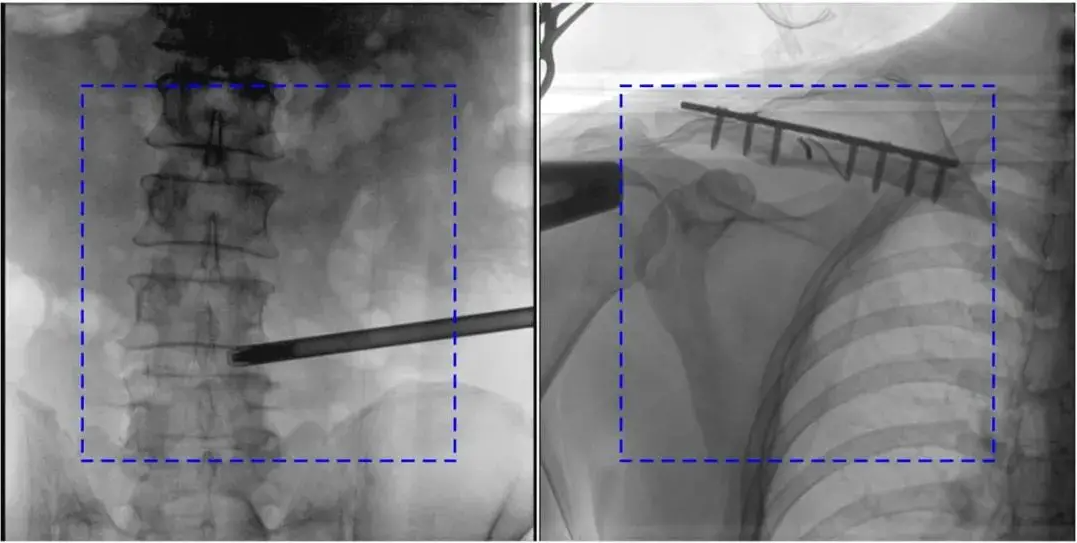

AEC模式下,金屬植入物或患者體位偏離視野中心可能導(dǎo)致曝光不足或過度。

解決辦法:手動調(diào)整曝光參數(shù),確保感興趣區(qū)域位于視野中央;避免金屬干擾,必要時調(diào)整患者體位。